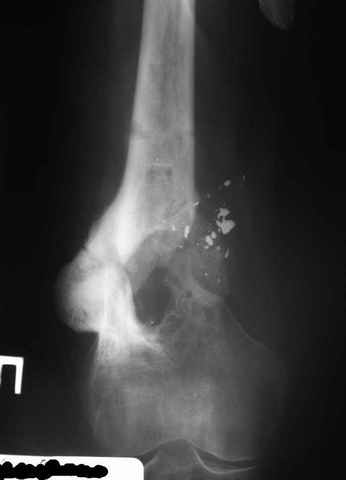

Возможно, проф. Лазарев предложит другой вариант, а в наших условиях мы бы закрыто заштифтовали бы бедро антеградно. Устранили бы варус, используя голень как рычаг, вероятнее всего, даже дистрактор не понадобился бы. В приницпе, можно и ретроградно ири наличии движений в колене, но варус будет труднее устранить - можно и предварительно аппаратом в таком случае.

Рефрактур уж точно можно будет не опасаться, а за несколько месяцев даже при отсутствии заполнения костью по всей окружности, этот обходной "мостик" упрочнится и возьмет на себя нагрузку. В приложении пример такого рода "эндопротезирования диафиза", прошло больше 3 лет.